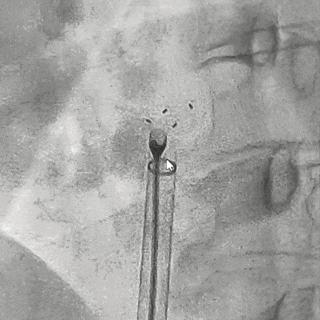

DSA下可见左盘及腰部3个Mark点靠拢

轻轻牵拉钢缆,DSA下可见4个Mark点整体随钢缆运动,判定锁定成功

前抵钢缆固定鞘管,逆时针旋转释放钢缆,DSA下4个Mark点聚拢